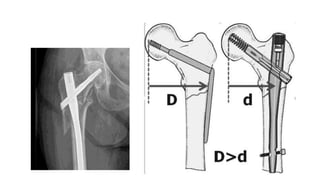

Treatment

• Stable fractures:

Close reduction with

DHS(Dynamic hip screw)

• Unstable fractures:

Close reduction

Gamma-nail(Small lever

arm)

Low Subtroch Fx’s

Most low subtrochanteric

fractures with an intact

piriformis fossa can be treated

with a 1st gen IM Nail

When piriformis fossa is not

involved and the lesser

trochanter is fractured, a 2nd

generation nail may be used

Nail or… Plate